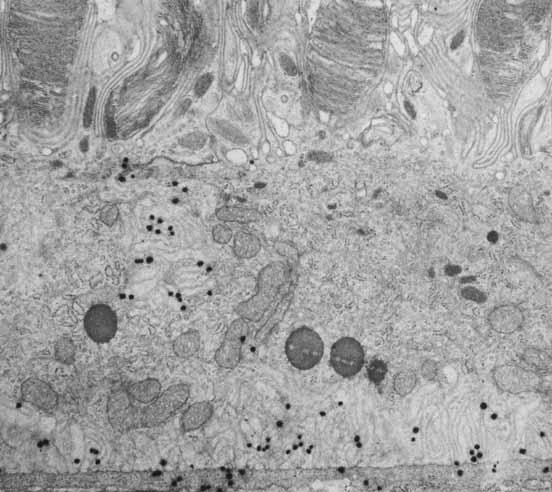

Insofar as the phototransduction process, by which light energy is converted into neuronal signaling, occurs in the neural retina, the details of that process are covered elsewhere in this series. However, there is a critical role for the RPE in maintenance of this process that bears discussion here. The light absorbing property of photoreceptor pigments such as rhodopsin is dependent on the presence of the vitamin A-derived ligand 11-cis-retinal. After light absorption, photoisomerization of 11-cis-retinal to all-trans-retinol occurs, however, the enzymes required for the re-conversion of all-trans-retinol to 11-cis-retinal are localized in the RPE, so that this transformation requires shuttling of these products between photoreceptors and the RPE in a process known as the visual cycle.48,49 RPE cells also concentrate retinoids from the circulation through specific transport properties (Fig. 13). Transportation of retinoids from photoreceptors to RPE is mediated by interphotoreceptor retinoid binding protein (IRBP), a major protein of the interphotorecptor space.50,51 Once endocytosed by the RPE, re-isomerization occurs before transport back to the neural retina. There still remains much to be learned regarding details of the mechanisms underlying aspects of the RPE cell's role in the visual cycle of retinoid accumulation and processing. Recently, however, additional important insights into the role of the RPE in the visual cycle process have been gained by elucidation of the role of the RPE65 protein. RPE65 was first identified as an RPE-specific protein following screening with libraries of anti-RPE monoclonal antibodies.52 RPE65 was subsequently identified as the product of the human gene causing Leber's congenital amaurosis (LCA), which is characterized by retinal degeneration in childhood.53 This was the first human genetic defect to be clearly associated with retinal degeneration as a result of a primary RPE defect. A mechanistic explanation for this connection, underscoring the critical role of the RPE in the visual cycle, was the identification of RPE65 as a specific binding protein for all-trans-retinyl esters.54

Fig. 13 Receptors for plasma retinol binding protein on the basal and basolateral membrane of the retinal pigment epithelium, visualized by autoradiography (silver deposits) of iodine-125-labeled retinol binding protein. (Bok D: Retinal photoreceptor-pigment epithelium interactions. Invest Ophthalmol Vis Sci 26:1659, 1985)